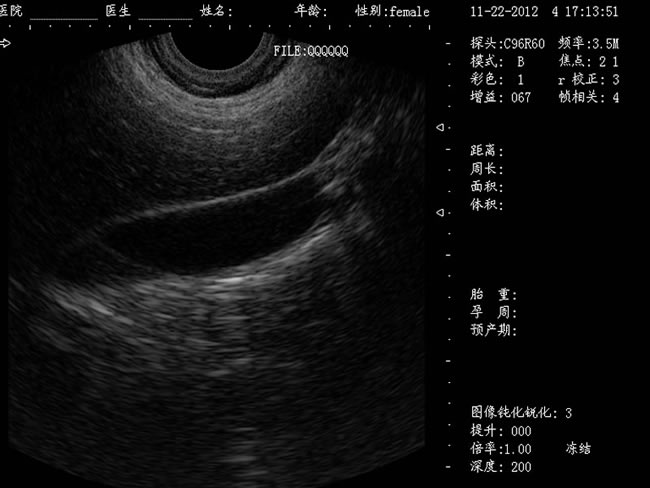

DW-400 全數(shù)字可視人流機(jī)

• 功能特點(diǎn): 定位精確 手術(shù)效率高:實(shí)時(shí)動(dòng)態(tài)頻率掃描等全數(shù)字超聲成像技術(shù)、生成精確的圖像引導(dǎo)手術(shù)器械迅速到大手術(shù)位置,避免損傷子宮內(nèi)膜和子宮穿孔的現(xiàn)象,即減輕了患者的痛苦又極大提高了手術(shù)效率。 高密度全數(shù)字波束形成:采用全新一代混頻技術(shù)、數(shù)字嵌入系統(tǒng)及數(shù)字整序技術(shù) 有效提升系統(tǒng)的穩(wěn)定性、可靠性:實(shí)時(shí)動(dòng)態(tài)孔徑成像,充分保證圖像的精度和清晰度。

定位精確 手術(shù)效率高:實(shí)時(shí)動(dòng)態(tài)頻率掃描等全數(shù)字超聲成像技術(shù)、生成精確的圖像引導(dǎo)手術(shù)器械迅速到大手術(shù)位置,避免損傷子宮內(nèi)膜和子宮穿孔的現(xiàn)象,即減輕了患者的痛苦又極大提高了手術(shù)效率。

有效提升系統(tǒng)的穩(wěn)定性、可靠性:實(shí)時(shí)動(dòng)態(tài)孔徑成像,充分保證圖像的精度和清晰度

a) CXA10R 腔內(nèi)探頭:152º可視可調(diào);